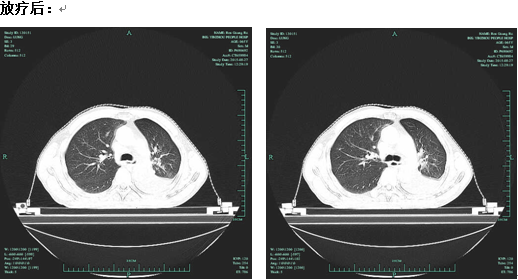

(以下为放疗前后对照CT)

立体定向三维调强放射治疗技术是精确放疗的一种治疗方式,它与常规的放射治疗相比,该技术需要医生付出更多的精力,更多的耐心和细心。徐正阳主任团队利用CT、MRI、X光片等影像技术,借助计算机的特殊软件反复对照,终于得到了病变在体内的精确空间位置。不仅如此,他们还为李先生认真反复计算,得出了控制肿瘤所需的精确的放射靶区剂量和次数,目的是使立体定向三维调强放射治疗技术能精确照射,从而帮助李先生杀灭肺门的肿瘤,提高他的生活质量。李先生自9月8号第一次采用放疗治疗至今,不仅没有出现放射性肺炎等严重并发症,而且病灶减小,左肺又重新张开了,心脏功能也恢复了正常。